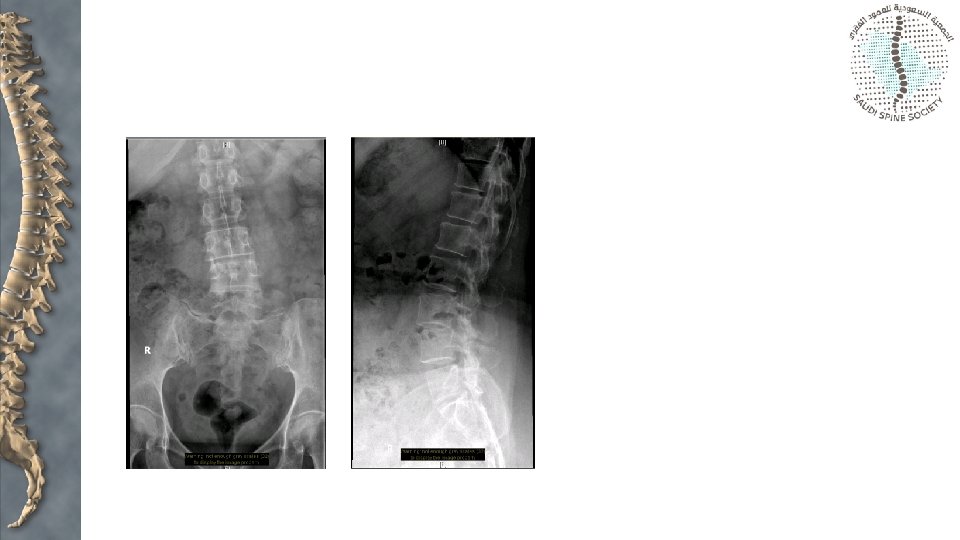

Assessment • X-rays: • Anteroposterior • Lateral • Oblique views

Assessment • X-rays: • Anteroposterior • Lateral